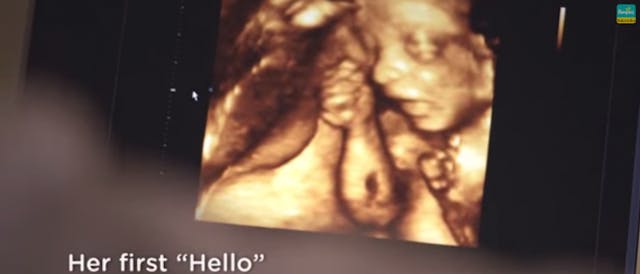

Have you ever wanted to share the miracle of human development with little ones? Live Action is proud to present the "Baby Olivia" board book, which presents the content of Live Action's "Baby Olivia" fetal development video in a fun, new format. It's perfect for helping little minds understand the complex and beautiful process of human development in the womb.